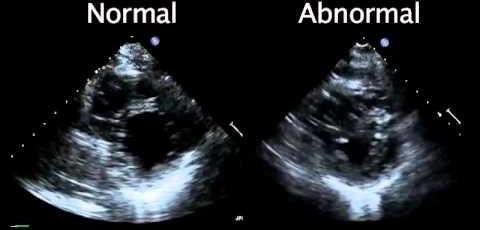

Echocardiogram: Essential Diagnostic Tool for Heart Conditions

An echocardiogram, commonly referred to as an “echo,” is a…